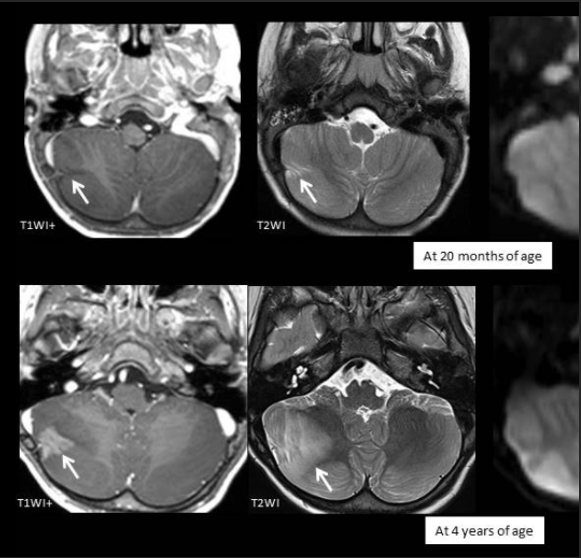

A 3-year-old child is admitted to the hospital due to decreased appetite and weight loss. She has been afebrile, and has not had vomiting or diarrhea.

Her activity level has decreased over the past two weeks.

She had been healthy until 2 months ago, when she was hospitalized for 48 ...

infection with mild respiratory distress and poor fluid intake.